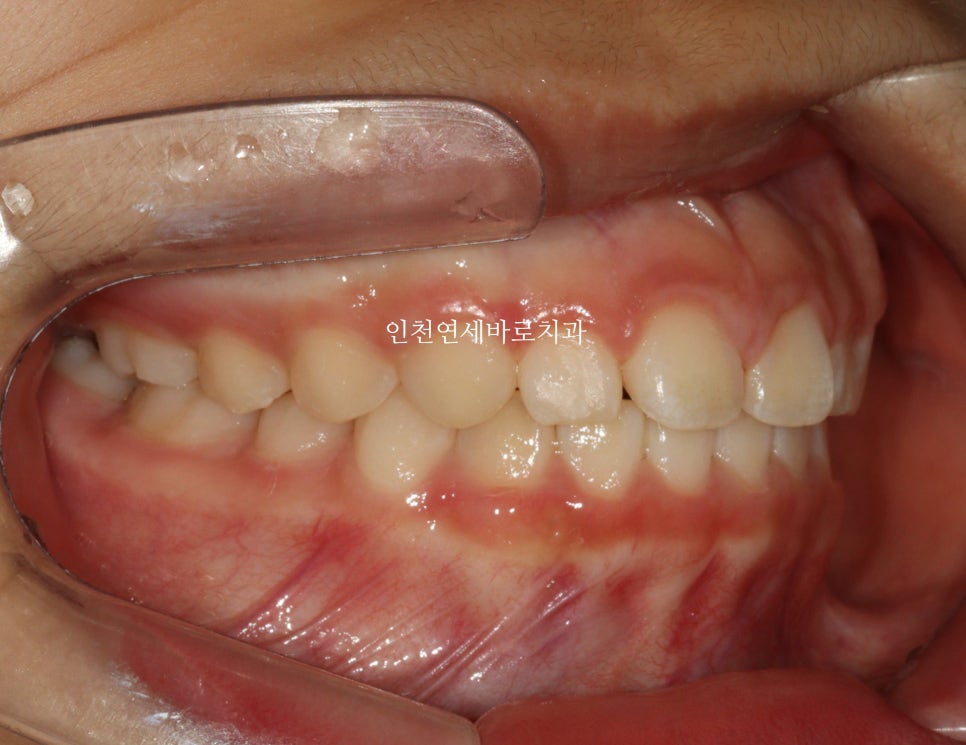

14주 후 결과

거의완성되었습니다.

거의 라고 말하는 이유는 저희 의료진 눈에는 아주아주 미세한 부분이 마음에 들진 않아서요.

인비절라인 라이트는 1년이라는 기간안에 1회 재제작이 아주 저렴한 비용으로 가능합니다.

이 친구도 정기검진을 하고 25.1.월쯤 아주미세한 부분의 수정을 위해 재제작을 하기로 했어요.

화살표 부분이 약간 아쉬웠기 때문입니다.

저런건 4주정도면 충분하죠.